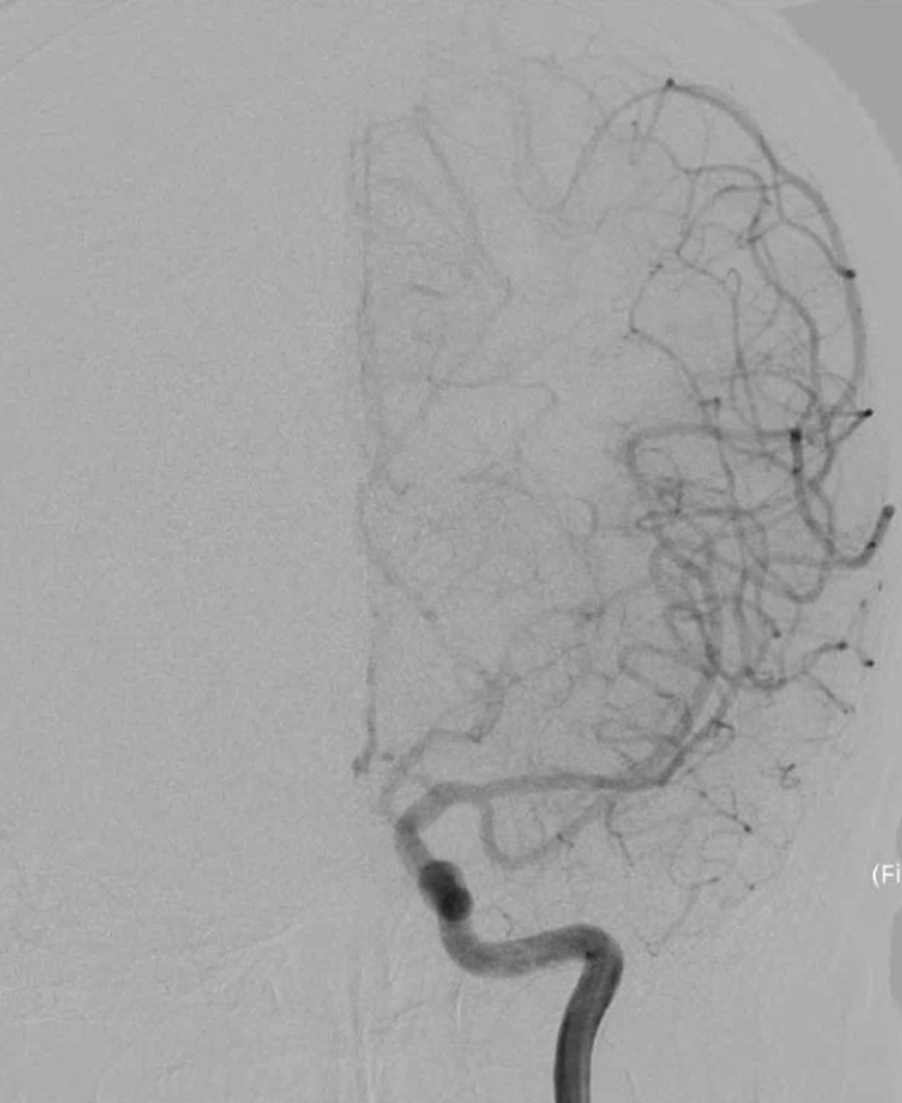

右侧颈动脉造影

左侧颈动脉造影

左侧颈内动脉重建(左侧狭窄及扩张较右侧更甚)

脑血管造影提示右侧颈内动脉颅内段多发动脉瘤(反主动脉弓)

脑血管造影提示右侧颈内动脉颅内段多发动脉瘤